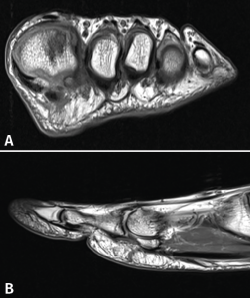

La artroscopia de la primera articulación metatarsofalángica es un procedimiento poco común con escasa experiencia publicada en la literatura. Sin embargo, los resultados reportados son alentadores y recogen un amplio abanico de posibilidades terapéuticas. En este artículo presentamos la experiencia de este procedimiento en un caso de osteocondritis postraumática de la cabeza del primer metatarsiano con un resultado excelente.

First metatarsophalangeal joint arthroscopy is an uncommon procedure with short experience published in the literature. However, the reported results are encouraging and reflect a wide range of therapeutic possibilities. In this article, we present the experience of this procedure in osteochondritis case of the first metatarsal with an excellent result.